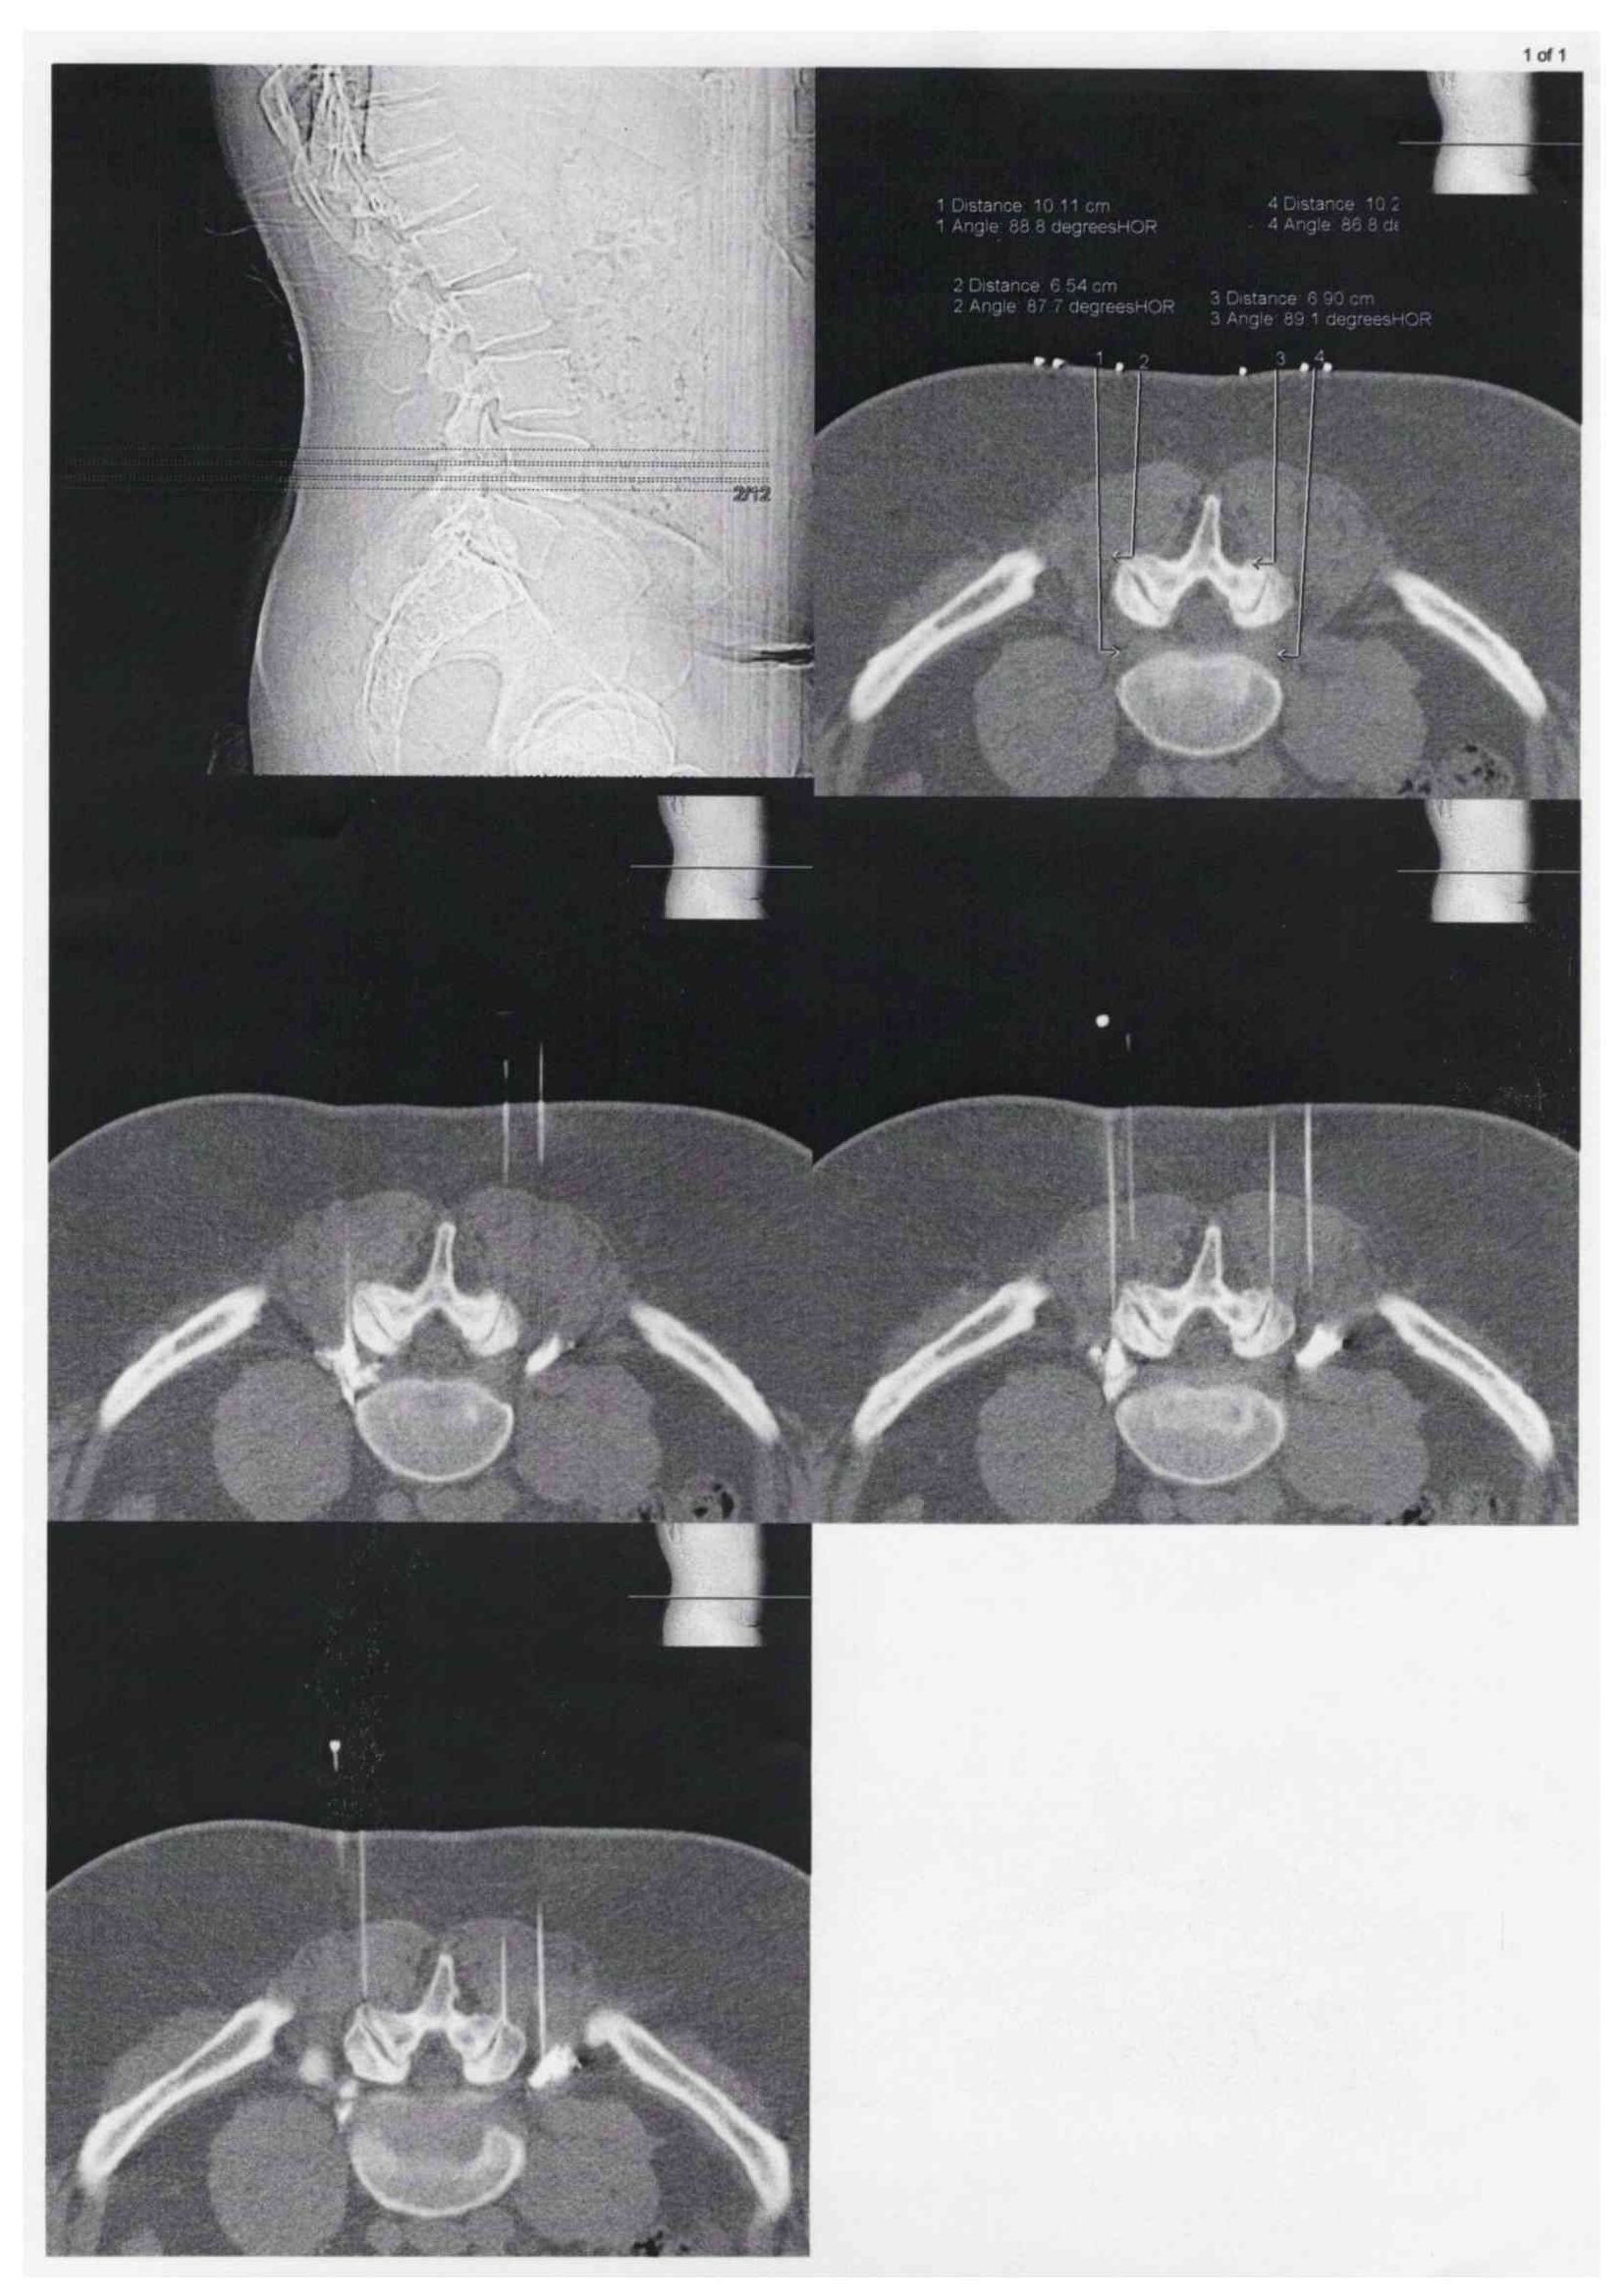

CT-gesteuerte Schmerztherapie

(PRT-Periradikuläre-Schmerztherapie und Facetteninfiltration)

Bei der CT-gesteuerten Schmerztherapie handelt es sich um ein besonders präzises Verfahren. So werden per computertomographischer Planung in Bauchlage des Patienten feine Nadeln millimetergenau an die schmerzenden Strukturen wie Wirbelgelenke oder Nervenwurzeln sowie ggf. auch an einen Bandscheibenvorfall herangeführt. Nach Kontrolle der Nadellage werden z.B. die Wirbelgelenke infiltriert oder aber ein Nervenwurzel mit betäubenden und entzündungshemmenden Medikamenten umspritzt.

Die Behandlung wird grundsätzlich in örtlicher Betäubung mit sehr feinen Nadeln vorgenommen. Der Patient liegt auf dem Bauch auf dem CT-Tisch. Zur genauen Höhenlokalisation der Schmerzstelle wird auf den Rücken ein Metallstreifen /Büroklammer geklebt. Ein so genanntes Topogramm, also eine Übersichtsaufnahme des entsprechenden Wirbelsäulenabschnittes wird angefertigt. Jetzt kann auf dem computertomographischen Schnittbild die Schmerzstelle lokalisiert werden. Auf dem Bearbeitungsmonitor können dann der exakte Eintrittspunkt der Nadel, der Winkel und die Tiefe, sowie die Stelle. in der gespritzt werden soll, ermittelt werden. All diese Parameter werden anschließend mit einem Laserpunkt auf dem Patienten dargestellt. Gefolgt von einer örtlichen Punktion nach steriler Säuberung der Haut kann die feine Punktionsnadel, die eine millimetergenaue Skalierung aufweist, am Schmerzpunkt platziert werden. Es folgt die CT- Kontrollaufnahme zur Dokumentation der exakten Nadellage. Um das Verteilungsmuster des zur verabreichenden Medikamente feststellen zu können, wird eine kleine Menge von verdünntem Kontrastmittel gespritzt. Dann werden Medikamente um die Nervenwurzeln verabreicht (PRT= Periradikuläre Schmerztherapie).